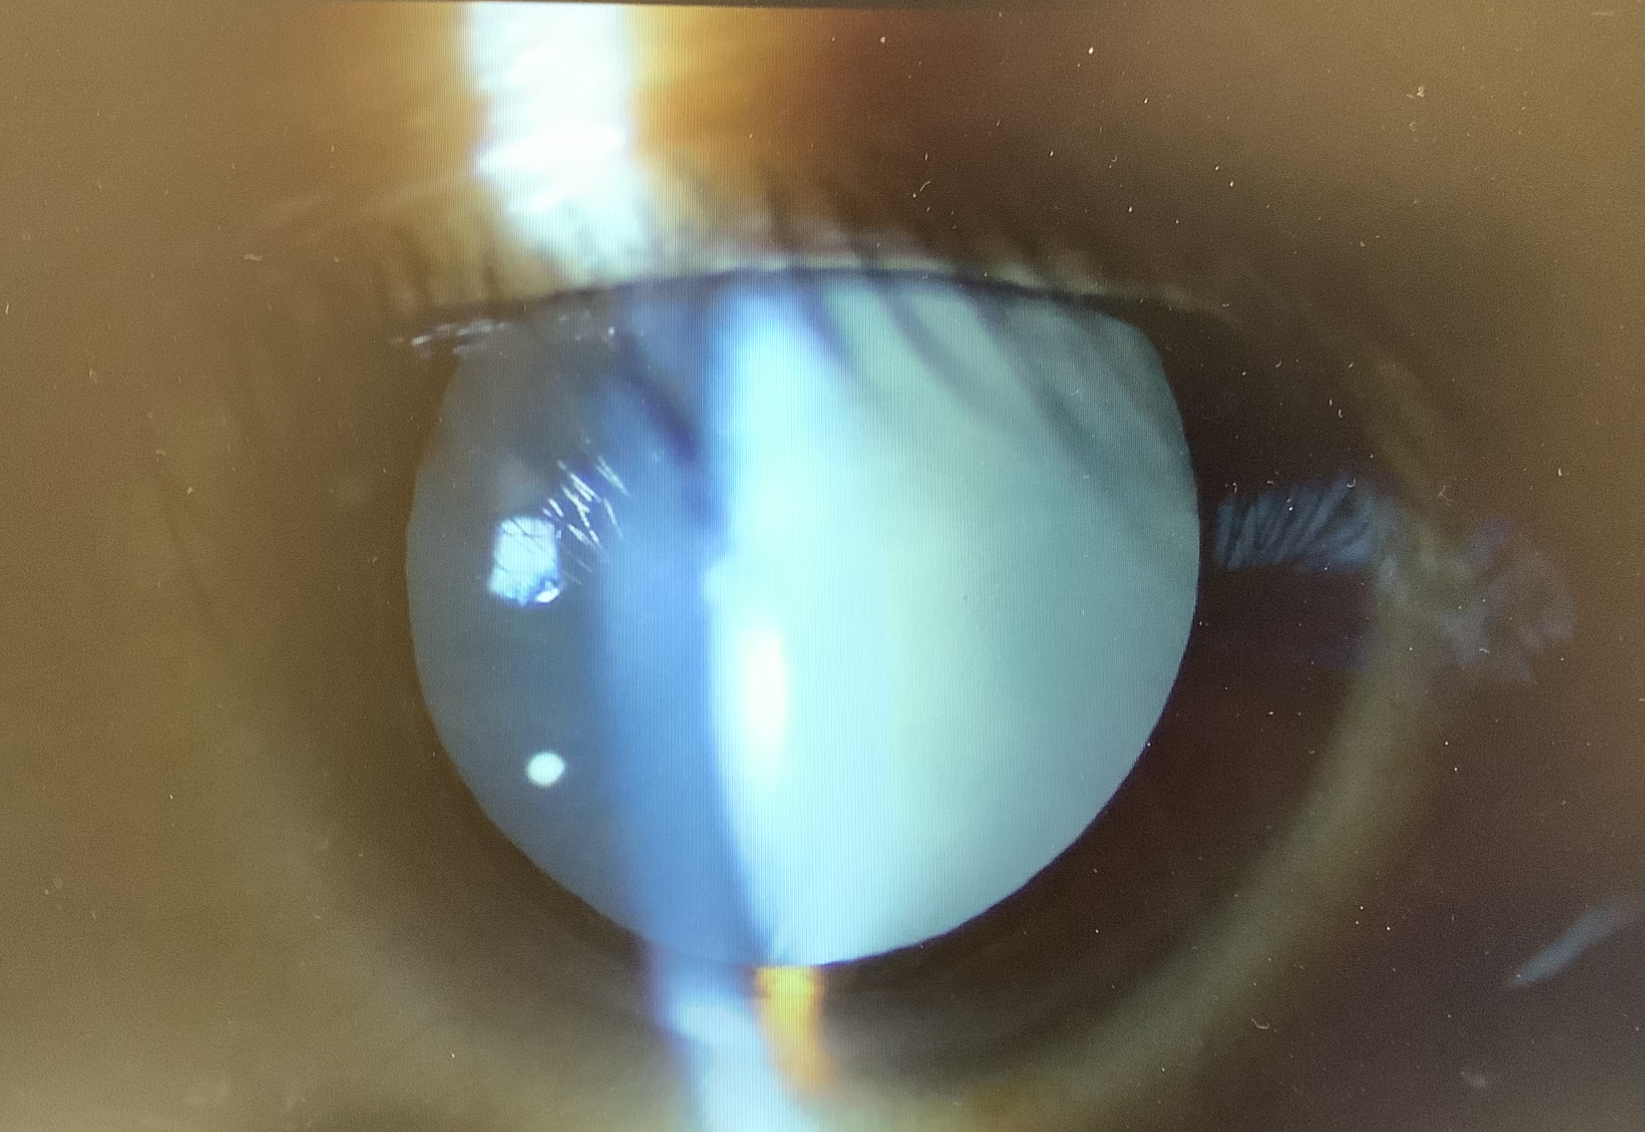

白内障の手術を受けた41歳の男性は、水晶体が真っ白になってしまっている“成熟白内障”でした。

通常の白内障は水晶体が濁ると言ってもある程度、光を通し、眼底からの光の反射(徹照)を利用することで手術する部分を詳しく見ることができます。しかし、成熟白内障ほど水晶体が濁ってしまうと、徹照が得られず、非常に見えにくい状態で手術を進めなければならなくなります。特に水晶体の表面を丸く切り抜く操作の連続円形前嚢切開(CCC)が、見えにくい状態でしなければならないのと、通常、成熟白内障では水晶体内部の圧が上がっていて、CCCの切開部がどんどん外側に流れる方向に進んでしまうことで、難易度が高い手術になってしまいます。そのため、成熟白内障の手術では前嚢を青い液で染めて見やすくし、僕は普段、針でCCCを行いますが、最初のきっかけだけ針で作り、白く液化している水晶体の濁りを速やかに針先から吸引し、ボリュームを減らした上で、その後はセッシで掴んでCCCを作ります。あとは、通常通りの手術になりますが、無事終わってよかったです。